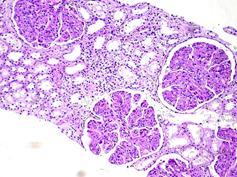

Рис. Мембранопролиферативный гломерулонефрит I типа.

A. Дольчатый вид клубочков за счет выраженной пролиферации мезангиальных клеток, увеличения мезангиального матрикса, стаза мононуклеаров и нейтрофилов в просветах капиллярных петель. PAS-реакция.